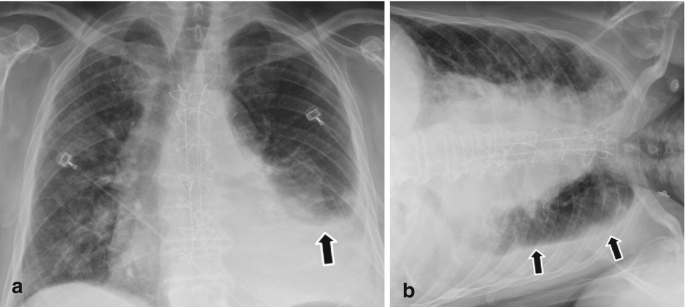

Recognition of pleural effusion on supine radiographs: how much fluid is required?

Imaging Subpulmonic Effusions - wikiRadiography

Pleural effusion is not always visible as a meniscus ... | GrepMed